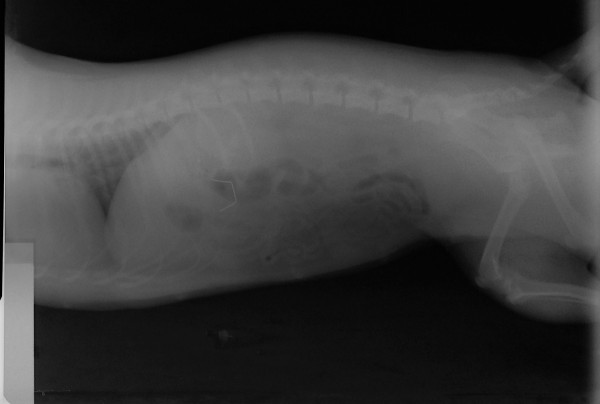

This time though, Hara's vomiting episodes were more serious and consistent. So,we decided to take a few xrays of Hara's.......belly!

..........and here is what we found!!!!!!!!!!

I have to confess, that it took us a few xray views and a thorough investigation of our xray plates, xray table and xray developing machine to convince ourselves and the owner that the object showing on the xray was really inside Hara's stomach and it was not an xray artifact!!!